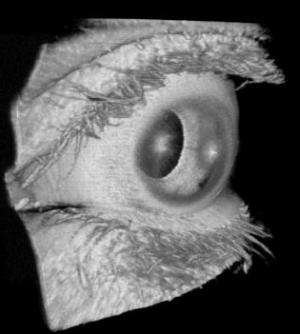

Practical examples include ophthalmology, where a 1.2 MHz A-scan rate can obtain a large scan of the retina before a patient blinks or involuntarily moves the eye. Another is cancer studies, where the team has demonstrated the imaging of rabbit esophagus, colon, and stomach at 1 MHz A-scan rates using a miniaturized OCT probe, as a translational step towards using the tunable VCSEL for human endoscopic cancer imaging.

"In an ophthalmic context, the VCSEL has demonstrated retinal scanning at an A-scan rate of 580 kHz with a wavelength tuning range of 83 nm and axial resolution of 8.9 microns in tissue, providing an image range appropriate for retinal imaging," said Potsaid. "Scanning the anterior eye requires a longer imaging range, but this is achievable without compromising resolution by configuring the same VCSEL to run slower while maintaining the same spectral sweep range."

To go further still and image the full length of the eye, the VCSEL can be slowed down to 50 kHz and the wavelength tuning range reduced to 45 nm. This does compromise the resolution slightly, but delivers an imaging range sufficient to include the entire length of the eye, from cornea to retina.